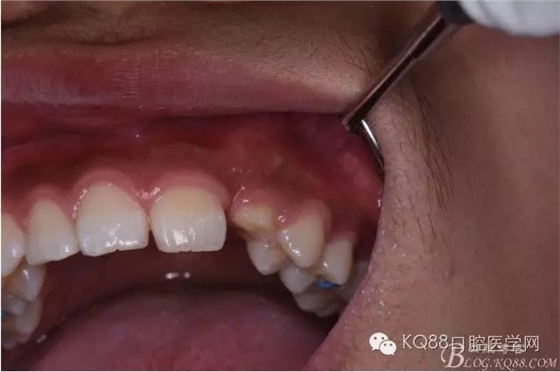

圖6.口內(nèi)觀:63滯留、23未見(jiàn)萌出。

640.webp (5).jpg